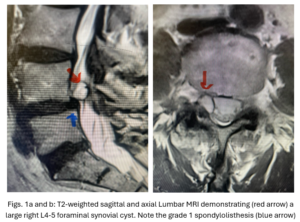

Figs 1a,b: T2-weighted sagittal and axial MRI demonstrating (red arrow) a large right L4-5 foraminal synovial cyst. Note the grade 1 spondylolisthesis (blue arrow)

This 54-year-old female with a long history of low back pain presents with three weeks of a progressive right footdrop with associated numbness and tingling of the right leg. In addition, she had right lateral hip pain down to the dorsum of her foot. She first noticed her right foot slapping the floor when she walked. She had no prior trauma or unusual activity before this began. Her chiropractor, who had treated her back pain for a long time, first noticed the foot drop and referred her for further evaluation. She presented with ⅖ strength in her right dorsiflexor. MRI revealed a large right L4-5 foraminal synovial cyst with some mass-effect on the thecal sac. (Fig. 1) She also had an associated grade 1 spondylolisthesis. Because the cyst was more foraminally-oriented, it had the majority of its effect on the right L4 nerve root. It was felt the patient required surgery to attempt to reverse her weakness. We performed a decompressive laminectomy at L4, removing the inferior facet process on the right in order to gain lateral and foraminal access to the right L4 nerve root. In the lateral recess there was a heap of inflammatory tissue which we entered, revealing the cyst. The medial wall was stuck to the dura. We internally decompressed the cyst which was mainly gelatinous material with some fluid. We dissected and removed as much of the cyst we could safely remove but left the medial wall for fear of removing it would cause a CSF leak, upon removing the bulk of the cyst we encountered anteriorly the descending and exiting right L4 nerve root which was purplish in color and clearly inflamed. We performed a generous foraminotomy of the right L4 as well as the right L5 nerve root. We also performed an instrumented fusion at L4-5 (Fig. 2).